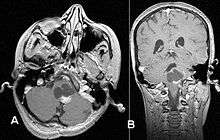

Pilocytic astrocytomas are often cystic, and, if solid, tend to be well-circumscribed. It is characteristically easily seen on CT scans and MRI.

Usually—depending on the interview of the patient and after a clinical exam which includes a neurological exam, and an ophthalmological exam—a CT scan and or MRI scan will be performed. A special dye may be injected into a vein before these scans to provide contrast and make tumors easier to identify. The neoplasm will be clearly visible.